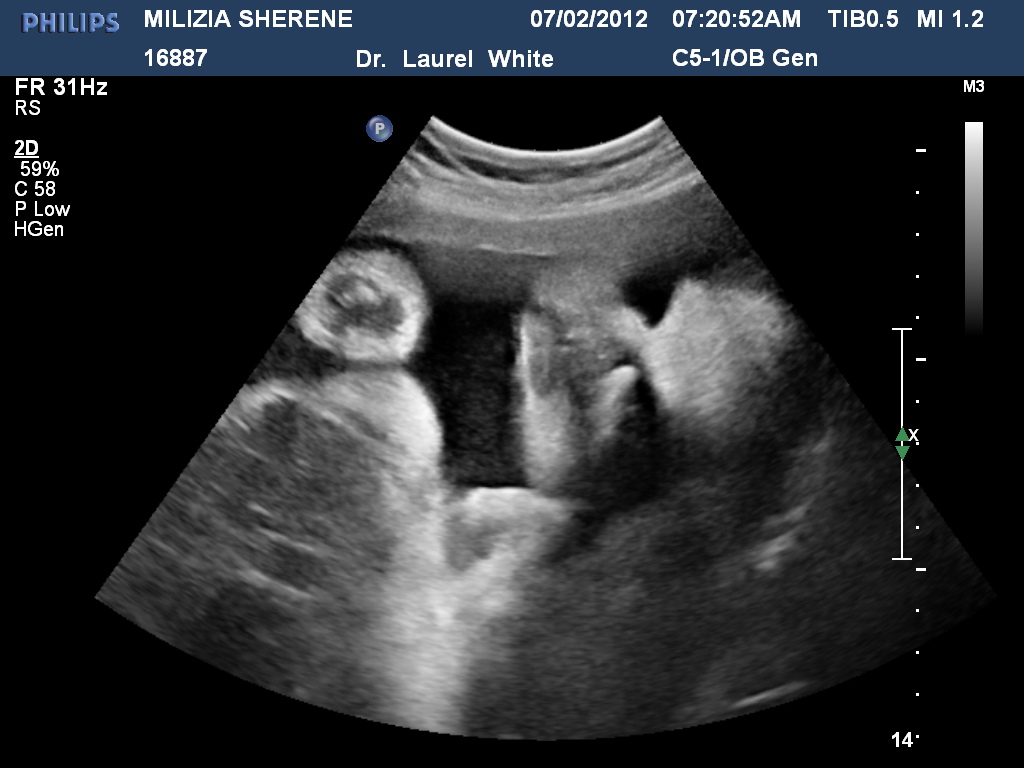

Ecografia 4D 32 Embarazo de 32 semanas latidos cardiacos Clinica actualizar

Baby boy 4d Ultrasound | 32 weeks pregnant - YouTube Último

Veamos 4D ultrasound 32 weeks pregnant face 4D Rafael Ortega Muñoz MD Ciudad

Mira Ecografia 4D embarazo de 32 semanas cara 4D - YouTube actualizar